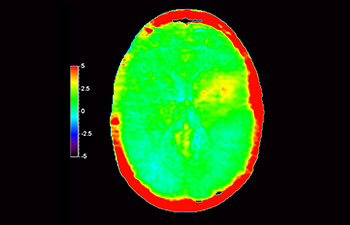

Lésion cérébrale

avec 3D APT